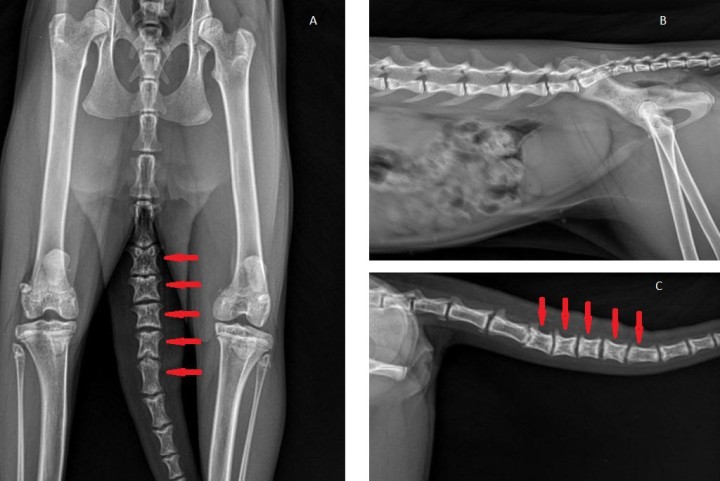

Al presentar cojera de la extremidad posterior izquierda, con dolor a la exploración de la rodilla izquierda, es recomendable la realización de proyecciones radiográficas ortogonales de dicha articulación, además de radiografías de columna lumbar y pelvis para descartar otras causas de cojera (Fig. 3).

<p>Proyección ventrodorsal de pelvis incluyendo vértebras caudales y rodillas (<strong>A</strong>), lateral derecha de columna lumbar, sacro (<strong>B</strong>) y vértebras caudales (<strong>C</strong>) donde se observan placas epifisarias ensanchadas y menor longitud de vértebras caudales (flechas rojas).</p>

Proyección ventrodorsal de pelvis incluyendo vértebras caudales y rodillas (A), lateral derecha de columna lumbar, sacro (B) y vértebras caudales (C) donde se observan placas epifisarias ensanchadas y menor longitud de vértebras caudales (flechas rojas).

Ante la sospecha de una osteocondrodisplasia, está indicado realizar radiografías de la cola para valorar vértebras caudales, de los carpos, metacarpos y falanges, así como de los tarsos, metatarsos y falanges (Figs. 4 y 5). Estas mostraron acortamiento de vertebras coccígeas, así como de los huesos metacarpianos, metatarsianos y falanges, y deformación y degeneración articular a esos niveles.